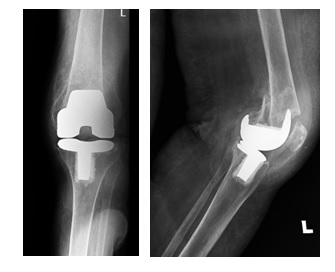

89-letnia chora po urazie stawu kolanowego doznanego w wyniku upadku z własnej wysokości. Wskaż właściwe postępowanie:

Pytanie 54